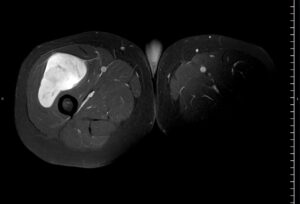

RM t1 supresion grasa con gadolinIo IV

HALLAZGOS RADIOLÓGICOS